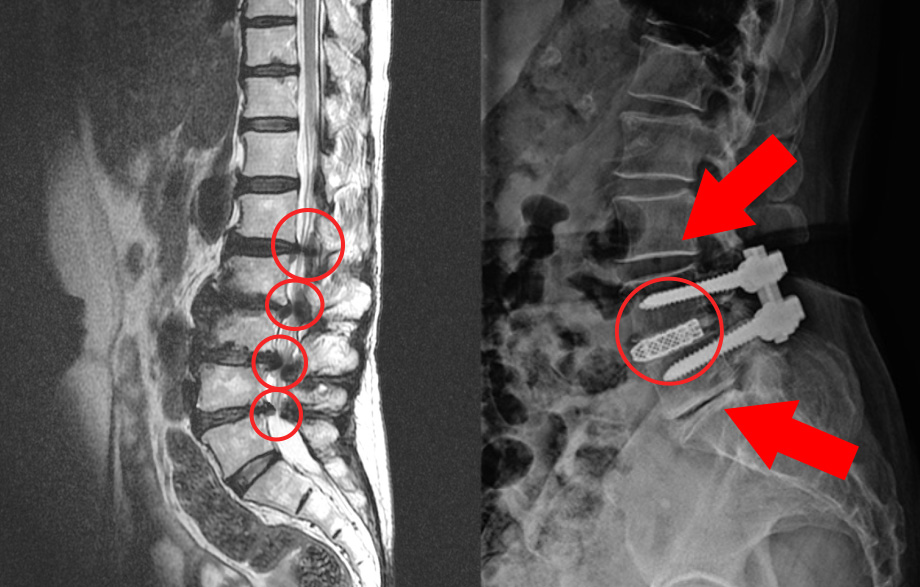

퇴행성 변화

가장 흔한 이유 중 하나는 퇴행성 변화입니다. 나이가 들어감에 따라, 척추의 디스크와 다른 구조물들이 시간이 지나면서 자연스러운 마모를 겪게 됩니다. 이로 인해 허리의 유연성과 지지력이 감소하게 되며, 척추관의 공간이 좁아지는 협착이 발생할 수 있습니다.

특히 중장년층에서 퇴행성 척추협착증이 빈번하게 발생하는 이유는 디스크의 수분 손실과 손상 때문입니다. 연세가 많은 분들은 특히 디스크의 수명이 줄어들고, 그로 인해 허리의 구조가 변형되며 신경이 압박을 받게 됩니다.